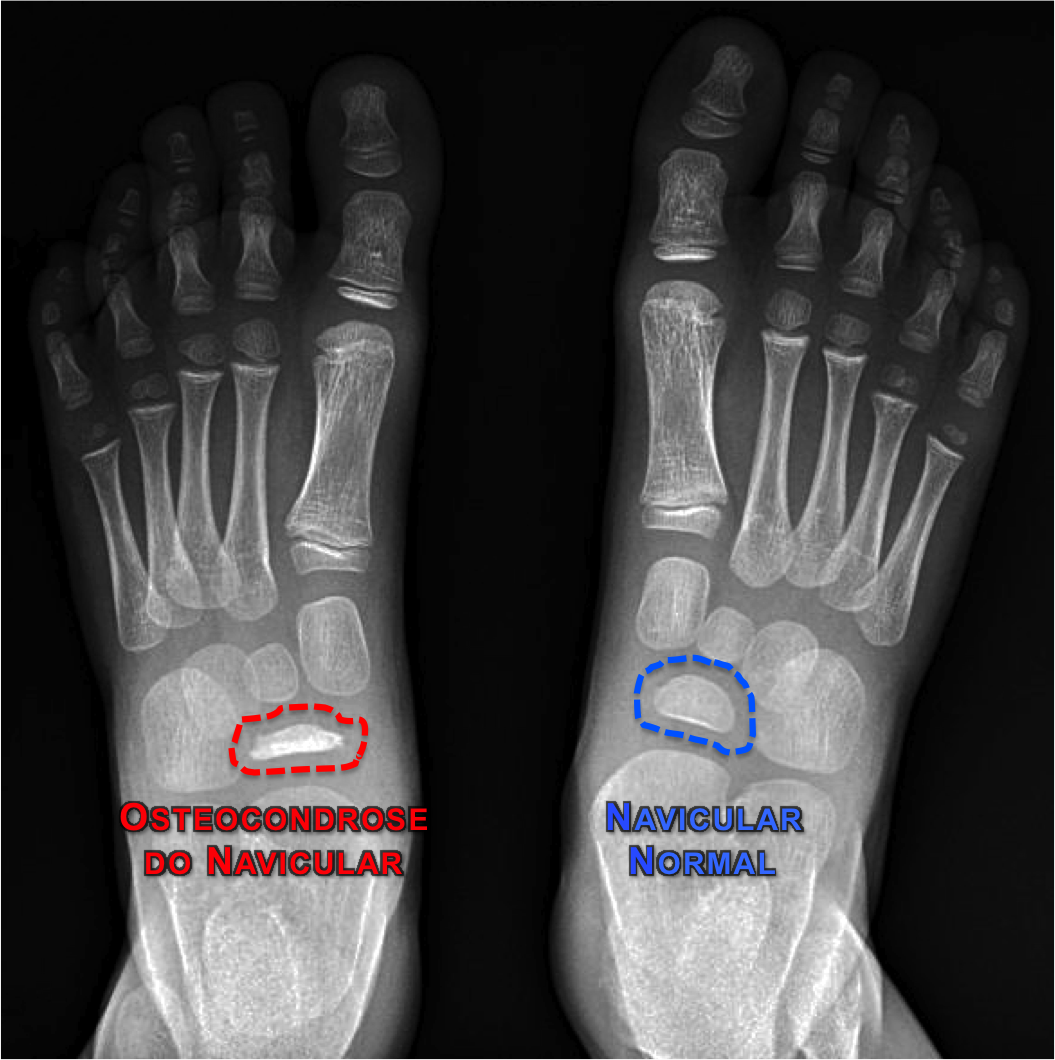

2. Osteocondrose do Navicular ( Doença de Köhler ):

Descrita por Köhler em 1908, a osteocondrose do navicular é mais frequente no sexo masculino (5:1); ocorre entre os 3 e 7 anos de idade, na maioria dos casos; e o acometimento bilateral é incomum.

O principal sintoma é a dor na região medial do pé que piora com o apoio. A região pode apresentar-se inchada e levemente avermelhada.

No exame radiológico podemos encontrar o osso navicular deformado, achatado e com múltiplas áreas de reabsorção e ossificação irregular (esclerose óssea).

O tratamento da osteocondrose do navicular é conservador, com a melhora dos sintomas em um tempo bastante variável. Medicação analgésica e anti-inflamatória, repouso e o uso de bota imobilizadora ou palmilha com o apoio do arco plantar, ajudam a diminuir a dor e o desconforto, além de abreviar o tempo de recuperação da lesão.

A doença de Köhler não ocasiona nenhuma alteração ou defeito ósseo no pé a longo prazo. O tempo de remodelação e reestruturação do navicular pode levar de 6 meses a muitos anos, sempre reconstituindo totalmente a sua anatomia.